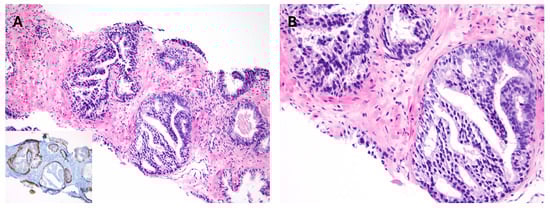

Figure 8.

(A,B) Atypical intraductal proliferation in biopsy confirmed by presence of basal cell marker expression (inset).

Atypical intraductal proliferation (AIP) shows architectural complexity and/or cytological atypia greater than that seen in high-grade prostatic intraepithelial neoplasia (HGPIN) but falling short of the morphologic criteria for IDC (Figure 8) [114]. Lesions that were formerly referred to as “cribriform HGPIN” are now classified as AIP [12,115,116]. AIP in biopsy is potentially a marker of undersampled cancer, including IDC, and of adverse pathological features in RP [114,117,118,119]. Several studies demonstrated overlap in ERG expression and loss of PTEN staining between AIP and IDC, showing that AIP and IDC can be part of a morphological spectrum and can be seen in transition [117,118,120]. Presence of AIP in biopsy, whether with low-risk prostate cancer or in isolation, should warrant repeat biopsy, including MRI targeting, to search for higher-grade cancer, including IDC.